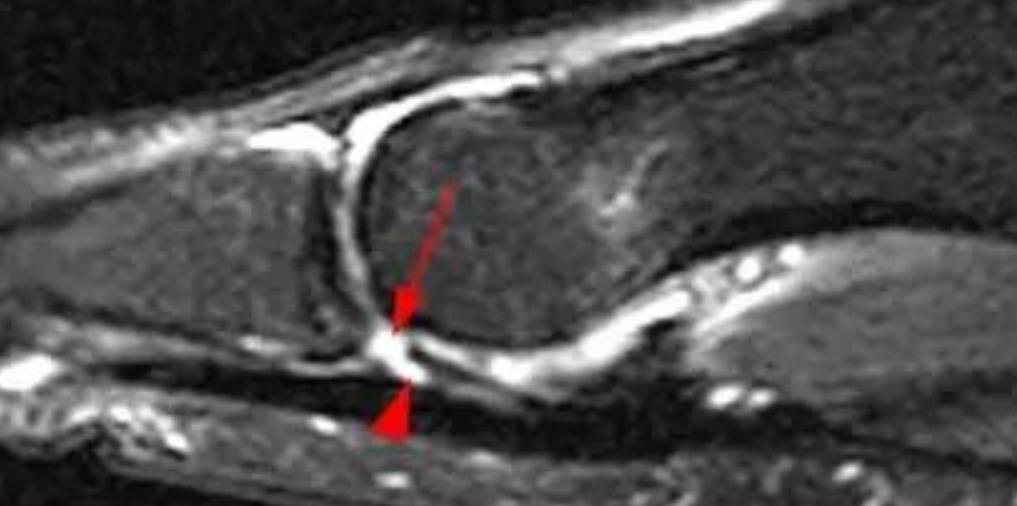

对患趾病史询问和体格检查对诊断至关重要。医师需要对第1跖趾关节的肿胀、瘀斑、畸形进行详细检查。对关节背侧、跖侧关节需要进行触诊检查。并且通过内外翻应力试验和前后方的抽屉实验来检查关节的稳定性。另外还应该检查关节的活动度。背伸时的阻力减少也表明了跖侧结构的损伤。对蹲趾背伸、跖屈力量的评估可帮助检测相关的韧带。现在用MRI来评估草皮趾的损伤程度已越来越常见。